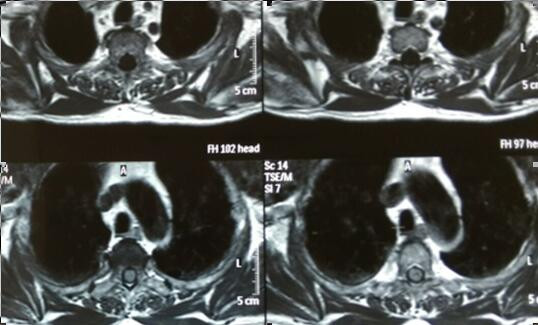

脊髓占位(胸3椎体水平)病变切除术

吴先生65岁,两年前无明显诱因出现双下肢麻木的症状,自行口服药物治疗无明显效果。入院前双下肢略肿胀。吴先生及家人慕名来我院就诊,行MRI检查示:“T3椎体水平脊髓内占位。”入院后查体及辅助检后,临床诊断为:脊髓占位性病变、颈椎病。于4月8日行脊髓探查、病变切除术。目前,吴先生切口愈合良好,肢体活动自如,生活完全自理。

手术难度:因患者为脊髓占位性病变,故手术需切开硬膜囊,探查脊髓,术中操作必须谨慎,若损伤脊髓可导致该节段以下的肢体运动、感觉障碍或瘫痪,若损伤神经根可导致单侧肢体运动、感觉障碍或丧失,需术中积极保护脊髓及神经根,手术风险极大。

术前胸椎MRI